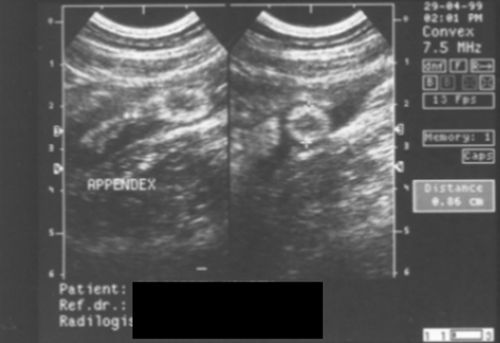

Siêu

âm rất chính xác (specific) trong việc xác định bạn không bị sưng ruột

dư, nếu siêu âm cho thấy rõ cái ruột dư của bạn hoàn toàn bình thường,

chả sưng to tí nào cả, ta có thể chắc ăn là bạn không bị sưng ruột dư.

Nhưng độ nhạy (sensitivity) của nó chỉ khoảng 86%, tức nó không khám phá

được 14% các trường hợp thực sự sưng ruột dư.